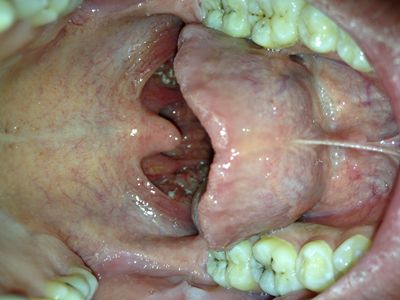

①接吻:在患者的嘴部及粘膜完好的前提下,礼节性的亲吻脸颊较低影响,但是口对口的接吻,尤其是深吻等,在嘴部及其粘膜出现破损和溃疡的时候,很有可能染上艾滋病病毒。